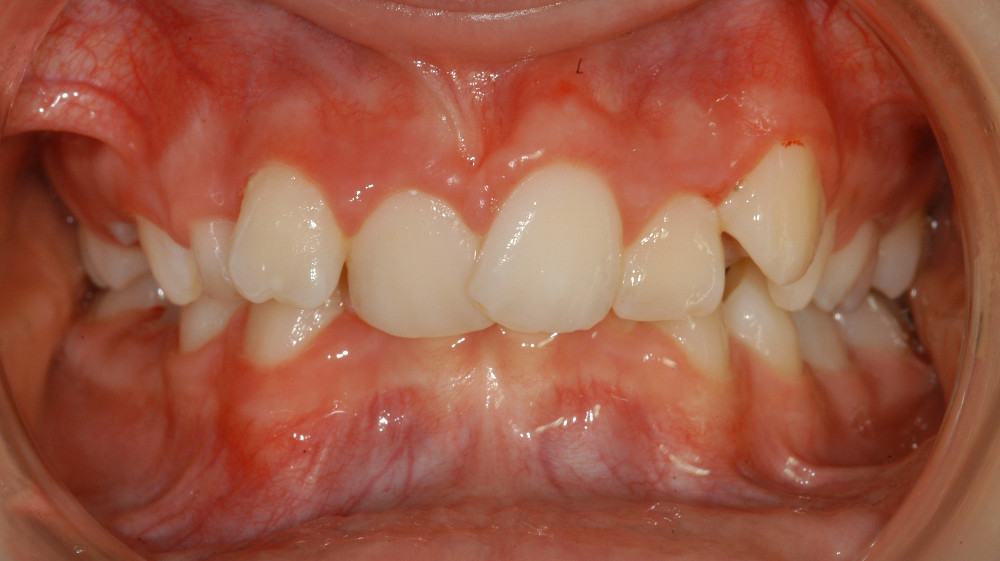

| Sehr schwere Kiefer-und Zahnfehlstellung Dauer ca. 2-3 Jahre, ev. mit Kieferchirurgie | Metalbrackets | ja | ja | Bild |

| ev. mit Chirurgie in Bern (Lindenhofspital) | Bild |